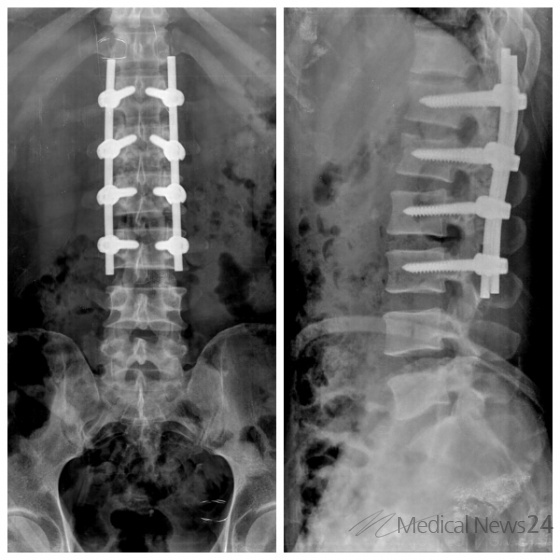

< MRI영상에서 보이는 제1요추 방출성 압박골절상태의 우즈베키스탄 환자의 척추영상>